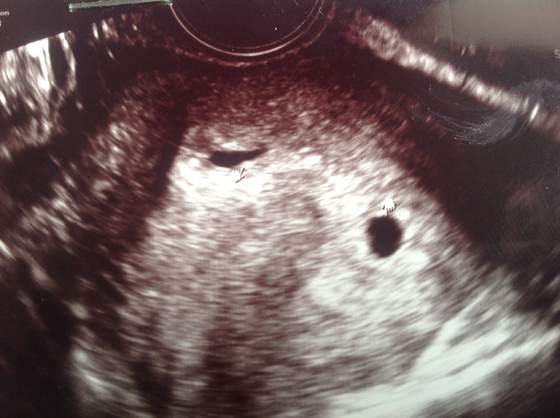

Zakrecona dzidzia sliczniuska, ach kocham takie foteczki.Nim sie spostrzegniesz a bedziesz czula juz ruchy i bedziesz misala pakowac torbe na porodowke. Ach walsnie mialam sie zapytac… to twoja pierwsza dzidzia?Bo nie masz suwaczka w stpoce.

Kira teraz dopiero doczytalam jak cudownie!!!!!!!! dwie kurusie!!!! Napewno beda dwie!!Widzisz tyle czekania,tyle staran na koncu nawet lekka utrata nadzieji a tu taka piekna NIESPODZIANKA